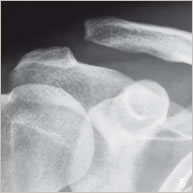

Lors d’un traumatisme au niveau de l’épaule, ces ligaments peuvent être rompus et le deltoïde désinséré. L’articulation acromio-claviculaire n’est plus maintenue, l’épaule et l’omoplate sont tirées vers le bas par la pesanteur et la clavicule est ascensionnée par les muscles (figures 2 et 5). On parle alors de luxation acromio- claviculaire responsable de douleur et de déformation visible.